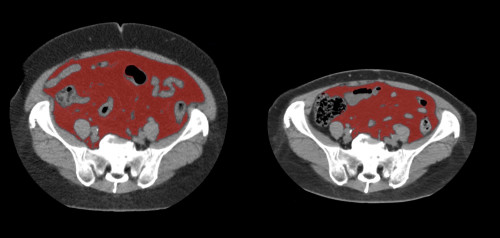

①

50代・女性(ご本人のご厚意で画像提供)

治療内容:チルゼパチド7.5mgの週1回自己注射による脂肪減少と脂肪肝改善

治療期間: 12ヶ月(52週)((用量は2.5mgから開始し最大で15mg。減量効果が得られる必要用量には個人差があります。))

費用:自由診療の場合は9900円(税込)×52(週)=514800円

想定されるリスク・副作用:下記に副作用を記載

※医療広告ガイドラインに準拠して表記

1:脂肪の減少

皮下脂肪の減少(赤色部分)